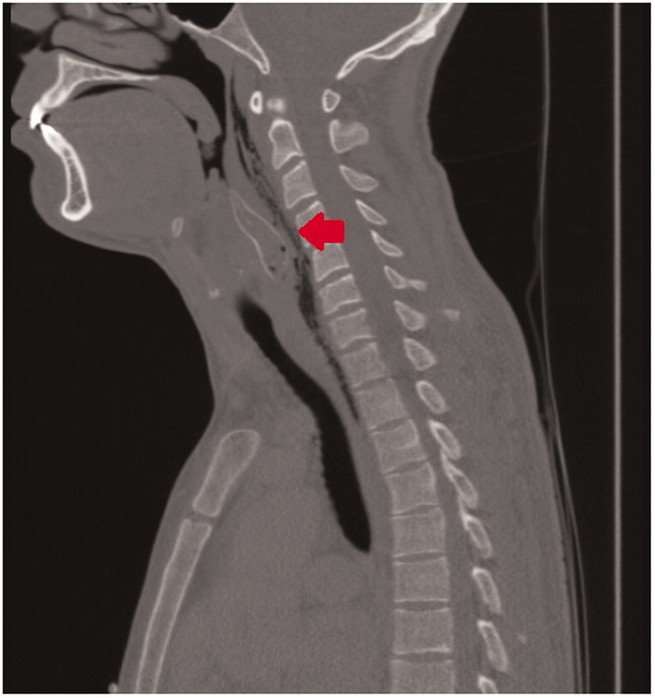

Ảnh chụp CT-scan vùng đầu cổ cho thấy một dị vật (mũi tên) dài ± 5 cm và ngang 1,5 cm ở hầu họng chàng thanh niên, ở thời điểm các bác sĩ chưa biết nó là một con cá.

Trở lại với chàng thanh niên người Hà Lan đã nuốt con cá chuột. Các bác sĩ cuối cùng đã phải gây mê cho anh, đặt ống nội khí quản và dùng ống nội soi để tìm con cá trong hầu họng của anh ấy.

Chàng thanh niên may mắn hơn khi không bị thủng thực quản, nhưng một phần thanh quản và thực quản đã bị phù nề tụ máu. Bệnh nhân sau đó tiếp tục phải thở bằng ống nội khí quản và đưa vào phòng hồi sức tích cực ICU để tiếp tục theo dõi.

Không lâu sau đó, các bác sĩ đã chụp CT cho anh ta và phát hiện vẫn còn một dị vật nữa trong họng khiến chàng thanh niên chưa hết phù nề. Họ lại phải gây mê cho anh ấy rồi nội soi để gắp nó ra.